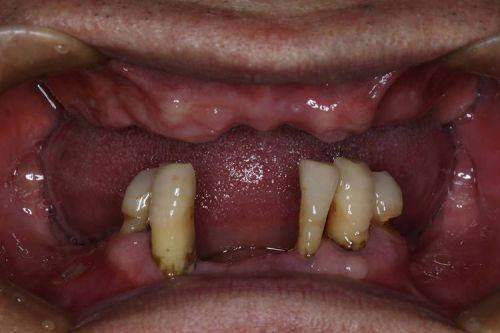

为了让大家更好地了解重庆团圆口腔医院李志锋医生开展的以色列种植牙项目,下面为大家分享一个患者实例。张先生是一位50多岁的患者,由于长期的牙齿缺失,导致咀嚼功能下降,面部也出现了一定程度的凹陷。他在朋友的推荐下来到了重庆团圆口腔医院。

李志锋医生为张先生进行了详细的检查后,建议他进行以色列种植牙手术。在与张先生充分沟通后,制定了适合他的种植方案。手术过程非常顺利,张先生在术后修复得也特别快。现在,张先生已经成功戴上了种植牙,他的咀嚼功能得到了明显改善,面部也修复了饱满。张先生对种植成效非常满意,他说:“没想到种植牙能让我的生活发生这么大的改变,感谢重庆团圆口腔医院和李志锋医生。”